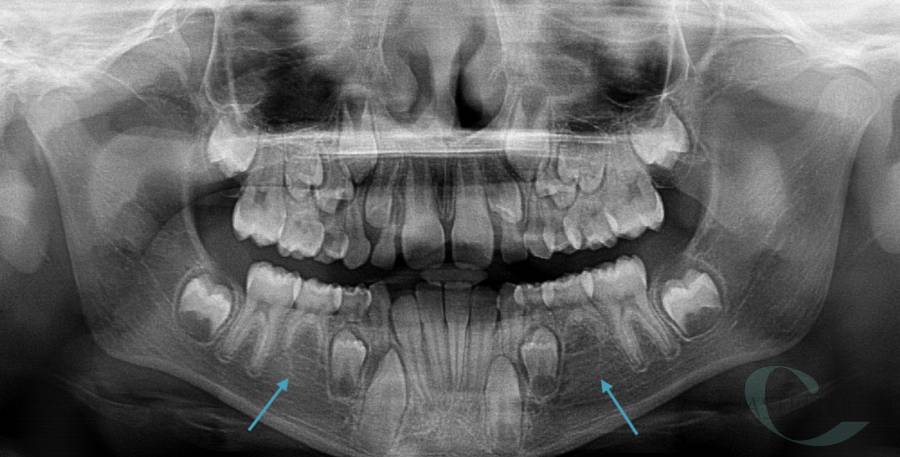

• Diagnosi e terapia delle alterazioni della permuta e delle alterazioni dento-scheletriche legate alle abitudini viziate in dentatura decidua, mista e permanente

• Terapia chirurgica degli elementi dentari decidui con ritardo di permuta

• Disinclusione chirurgica degli elementi dentari permanenti ritenuti